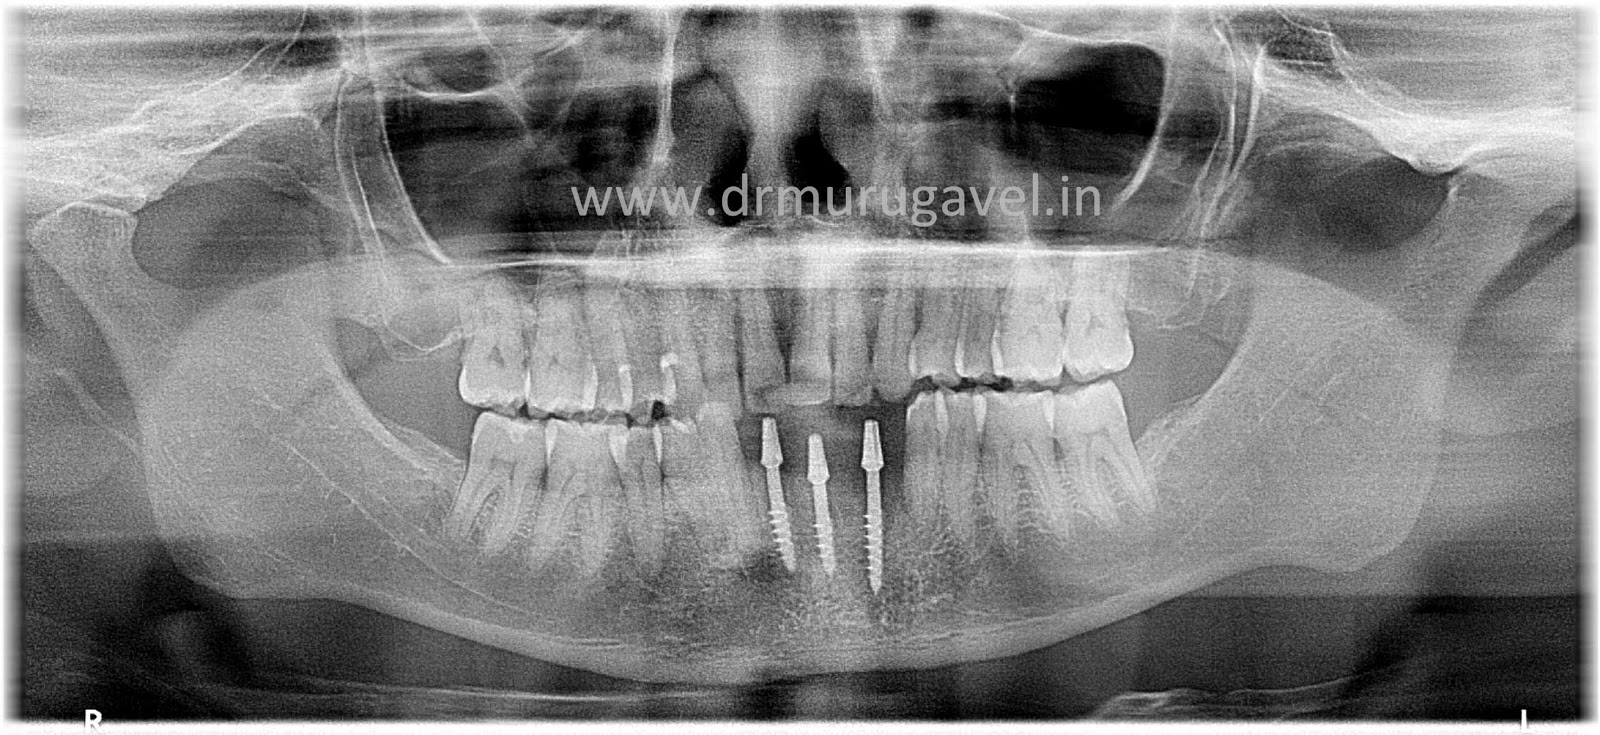

Preoperative OPG

Postoperative OPG